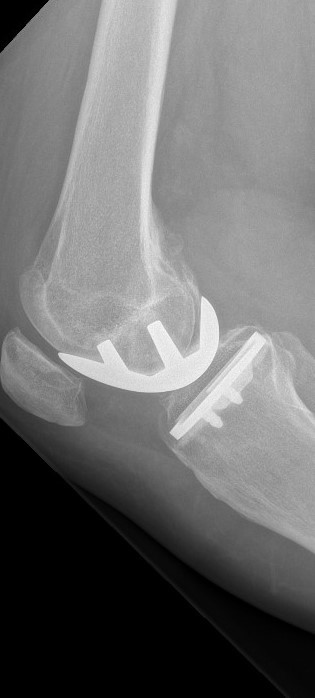

Das Kniegelenk besteht aus drei Gelenkkompartimenten: einem inneren, zentralen und äußeren Kompartiment. Die Kniescheibe bildet ein Widerlager und gleitet über den Oberschenkelknochen. Prinzipiell ist ein isolierter oder kombinierter Verschleiß vom inneren oder äußeren Gelenkkompartiment sowie auch dem Kniescheibenwiderlager möglich. Erkennt man die Erkrankung früh genug und ist der Leidensdruck entsprechend, so kann man die einzelnen Kompartimente isoliert ersetzen.

Wir halten ein großes Portfolio moderner und bewährter Prothesen vor, die sich entsprechend den o.g. Ausführungen vom Prothesendesign unterscheiden. Innerhalb des Designs liegen verschiedene Ausführungen und verschiedene Größen vor, so dass wir je nach Krankheitsbild für Sie eine individualisierte Versorgung anbieten können. Bei entsprechender Indikation kann der Kniegelenkersatz auch mit robotischer Unterstützung erfolgen, die Prinzipien werden in dem nachfolgenden Artikel aus FOCUS-Gesundheit 5/2023 verständlich dargestellt.

Sollte bei Ihnen eine Endoprothese in Frage kommen, wird durch Beurteilung verschiedener Faktoren der Prothesentyp aus dem o.g. Portfolio für Sie ausgesucht.

Während des Eingriffes wird Ihr Gelenk gegen ein künstliches Gelenk ausgetauscht. Der Eingriff dauert etwa ein bis eineinhalb Stunden und kann in Allgemein- oder Teilnarkose durchgeführt werden. Welche Art der Narkose für Sie in Frage kommt, wird Ihr Narkosearzt mit Ihnen besprechen. Durch das prä- und intraoperative Blutmanagement der Anästhesieabteilung werden Fremdblutkonserven normalerweise nicht benötigt. Am ersten postoperativen Tag werden Sie auf die Normalstation verlegt wo mit der Mobilisierung begonnen wird. Während des stationären Aufenthaltes werden Sie einen sicheren und selbständigen Gang wiedererlernen – in der Regel ohne Belastungseinschränkungen. Ein Hauptaugenmerk liegt in der Wiederherstellung der Beweglichkeit des Kniegelenkes. Bis zur Entlassung sollte ein Bewegungsausmaß von voller Streckung und mindestens 90° Beugung, unabhängig vom präoperativen Befund, vorliegen.